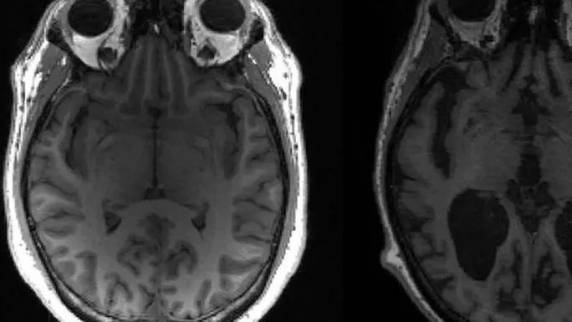

Pesquisadores do Instituto de Pesquisa de Demência do Reino Unido podem ter feito uma importante descoberta sobre a morte de neurônios provocada pela doença de Alzheimer. Em um artigo publicado na revista Science, a equipe associou as proteínas anormais que se acumulam no cérebro com a “necroptose”, uma forma de suicídio celular. As informações são da BBC Brasil.

Agora, porém, os pesquisadores do Instituto de Pesquisa de Demência do Reino Unido acreditam que a amilóide anormal começa a se acumular nos espaços entre os neurônios, levando a uma inflamação cerebral que é nociva para essas células e passaria a mudar sua química interna.

Assim, começariam a surgir emaranhados de TAU e teria início a produção de uma molécula chamada MEG3, que provoca a morte das células cerebrais por “necroptose”. A “necroptose” é um dos métodos que o corpo humano normalmente usa para eliminar células indesejadas à medida que células novas são produzidas.